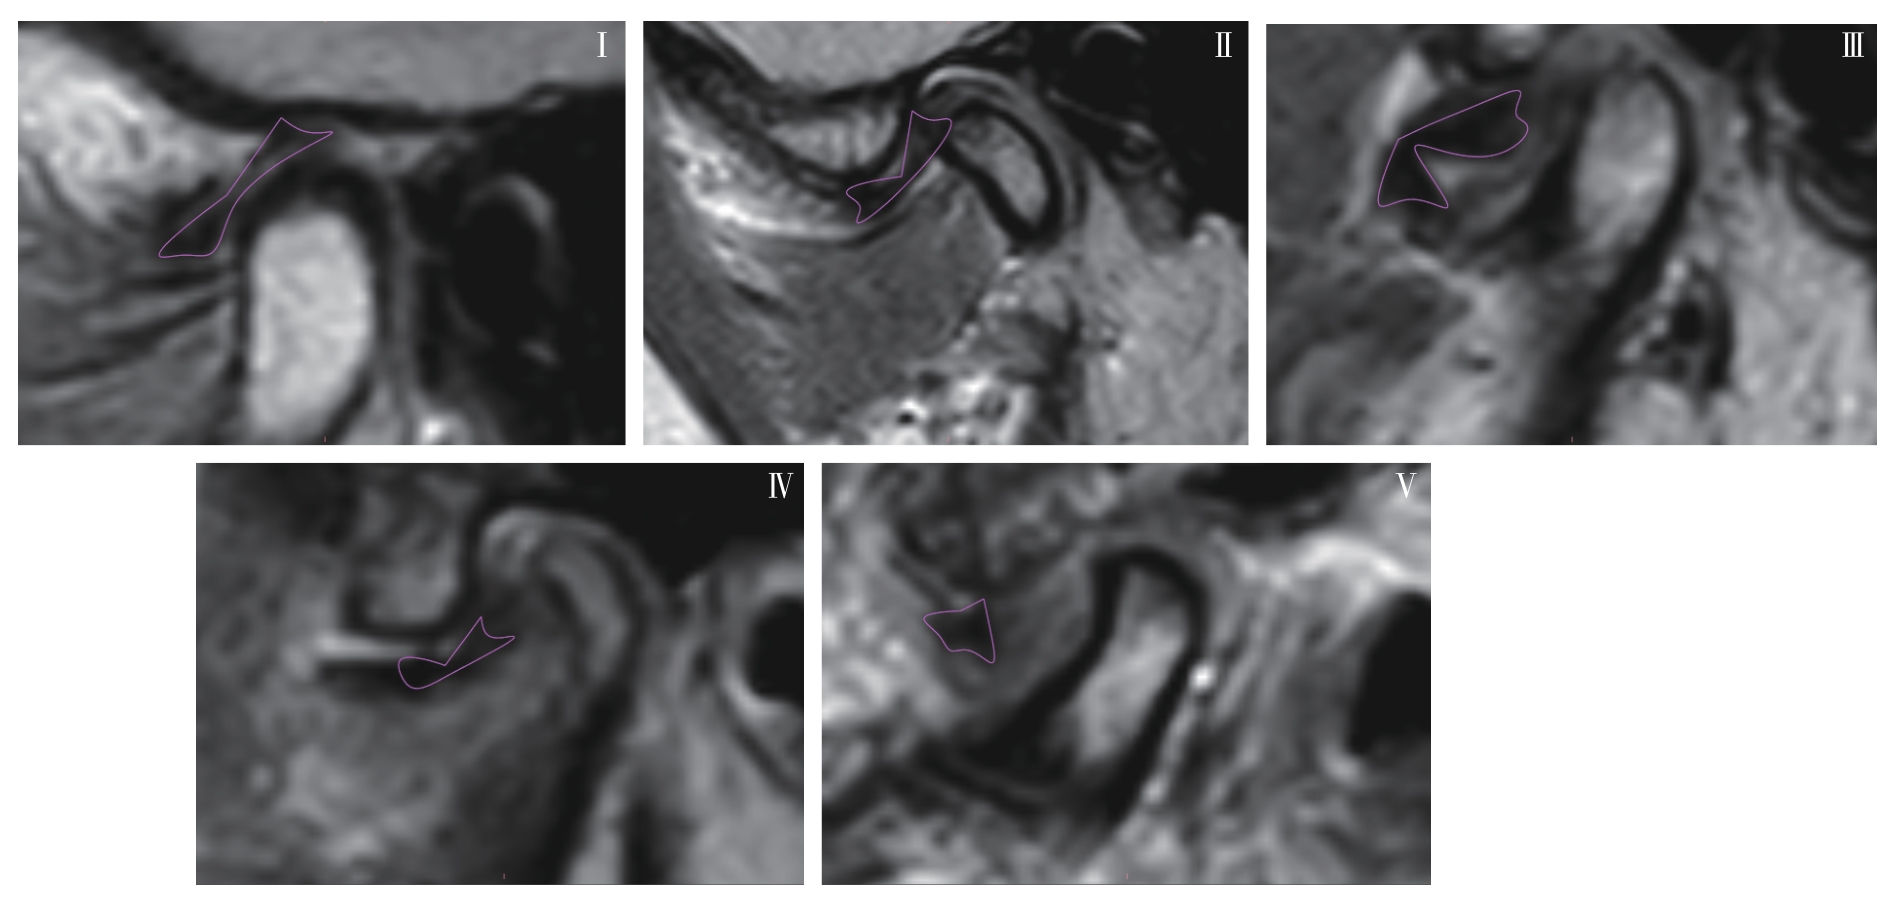

INCESU L, TAŞKAYA-YILMAZ N, OĞÜTCEN-TOLLER M, et al. Relationship of condylar position to disc position and morphology[J]. Eur J Radiol, 2004, 51(3): 269-273.

|

| [28] |

WANG M Q, CAO H T, GE Y L, et al. Magnetic resonance imaging on TMJ disc thickness in TMD patients: a pilot study[J]. J Prosthet Dent, 2009, 102(2): 89-93.

| [29] |

HU Y K, YANG C, XIE Q Y. Changes in disc status in the reducing and nonreducing anterior disc displacement of temporomandibular joint: a longitudinal retrospective study[J]. Sci Rep, 2016, 6: 34253.